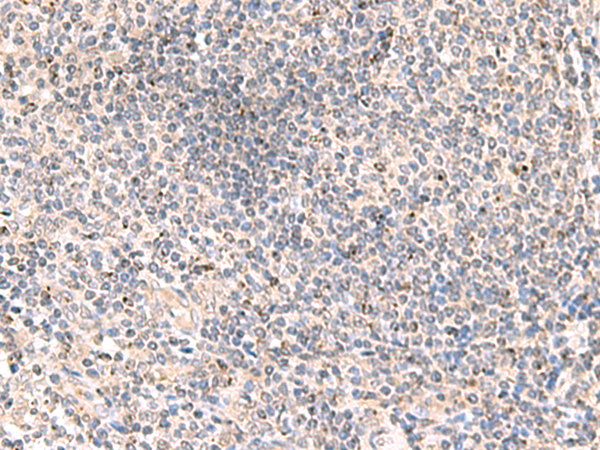

分类: 科研抗体货号: P10075别名: MLS; CCHL; MCOPS7; LSDMCA1应用: WB,IHC反应种属: Human, Mouse